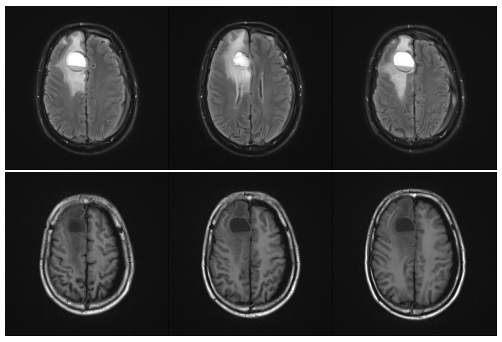

为了弄清病灶的“真面目”,县医院立刻安排了颅脑磁共振(MR)平扫及增强检查。影像画面清晰地显示,右侧额叶的病变范围不小,呈囊性改变,周围还存在典型的血管源性水肿带——所有迹象都指向一个令人担忧的方向:颅内恶性肿瘤的可能性很大。

术前核磁提示脑转移瘤